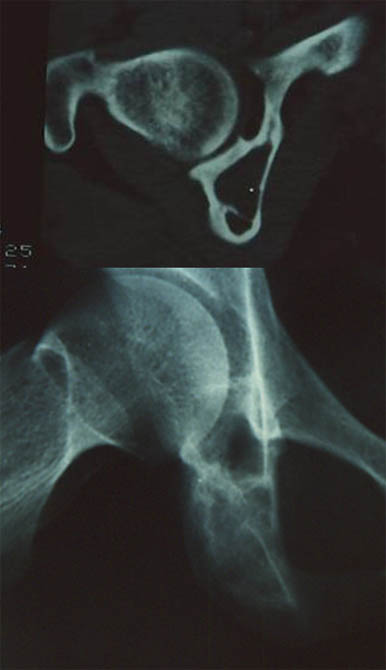

Hanche1

Hanche2

Garçons de 13 ans souffrant de sa hanche depuis 6 mois